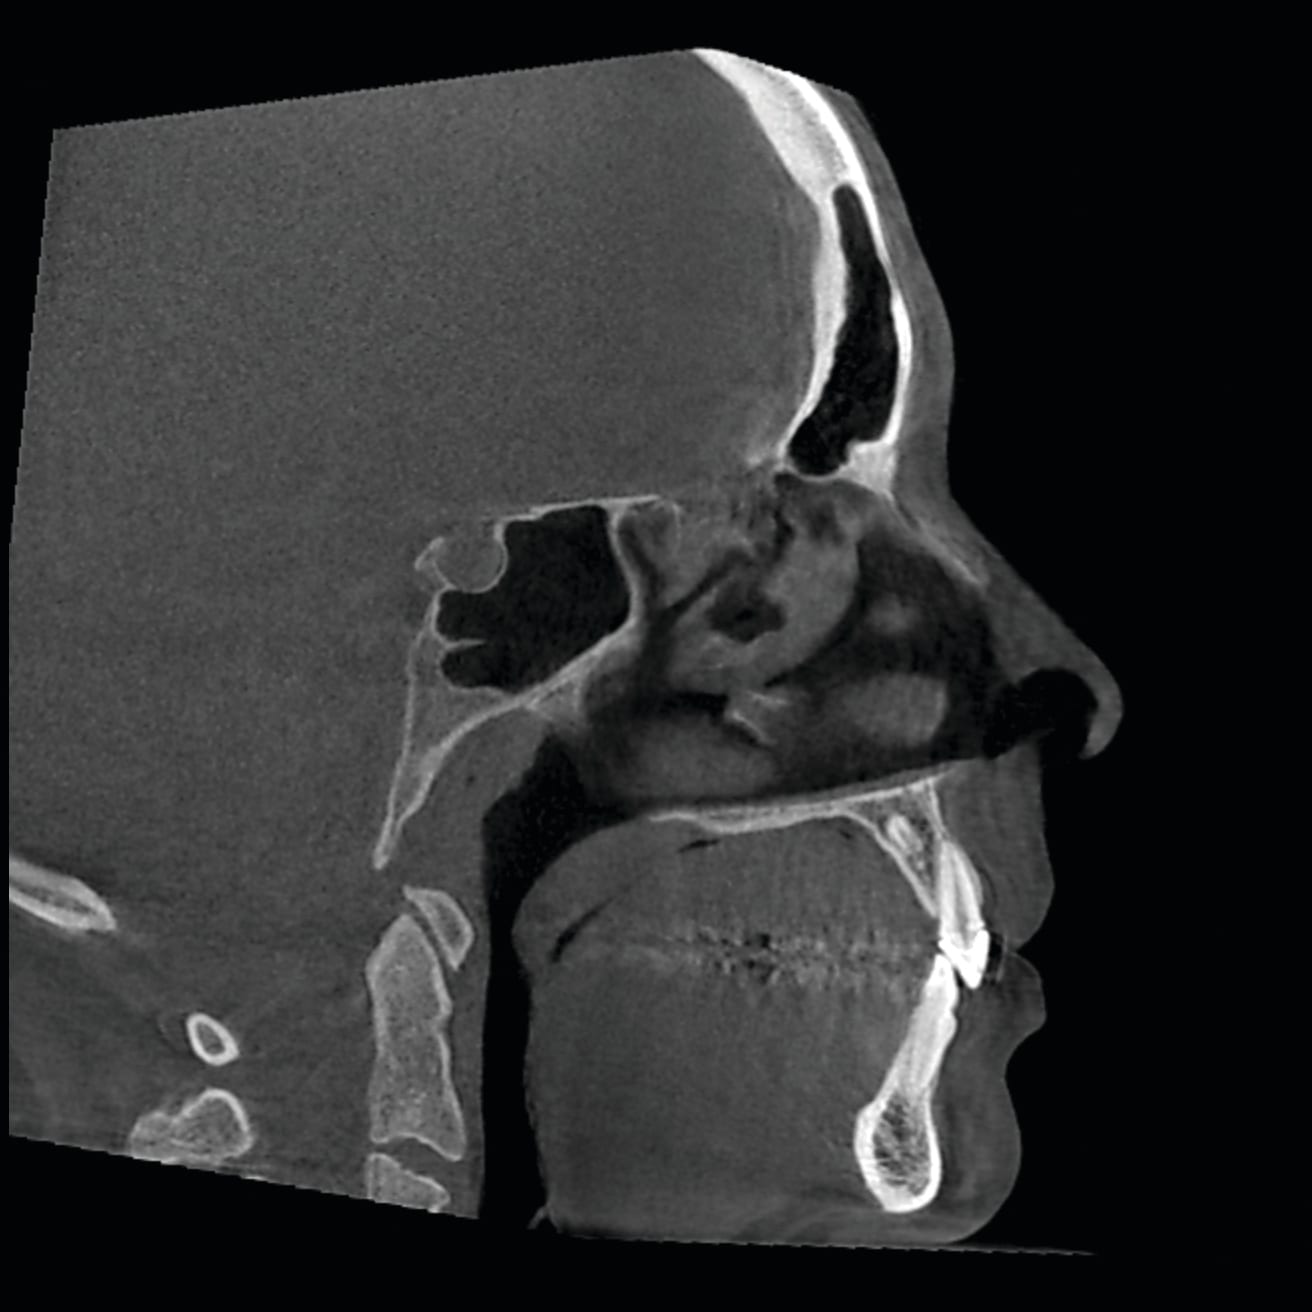

7. Any patient suspected of having an compromised airway. Granted, this is not known until the patient is scanned. However, if there is an inadequate airway, the location of the constriction could determine the type of treatment the patient receives. It could change the treatment plan from a camouflaged treatment to a mandibular advancement for example. A traditional ceph is not adequate in determining the size of an airway. The subject of imaging and treating compromised airway patients is experiencing more advancement in dentistry than any other subject. It is this clinician’s opinion that the orthodontic specialist should be the most qualified clinician to aid in the treatment of these types of patients. These patients deserve a multidisciplinary approach, perhaps more than any other type of patient we see in our practices. DICOM images are vitally important for the proper diagnosis and treatment of these individuals. Figure 28 and Figure 29 illustrate an example of this type of patient that had a chief complaint of overjet. She could be treated with the retraction of the upper anteriors. After further imaging, it was decided that a mandibular advancement would best serve her. Also note the osteophyte on C1 that is constricting the airway. This is not a common occurrence. This osteophyte needs to be removed. So the DICOM images changed our treatment plan. Figure 30 illustrates another patient seeking treatment after surgical relapse. This patient will need to be treated with surgery again. Note the restricted airway at the hypo pharynx. This must be treated prior to the re-treatment of this case. Also note the upper centrals have been torque through the lingual cortical bone. These two problems are not viewed with conventional 2D images.